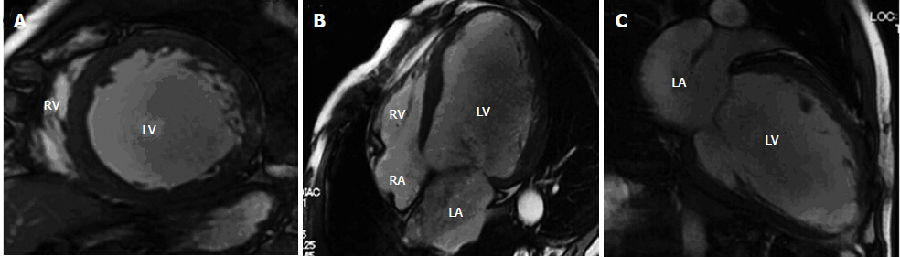

扩张型心肌病患者代表性的电影-心脏磁共振图像。图像显示中室短轴线(A),水平轴(4-室)(B)和垂直长轴视图(C)。图像显示左心室(LV)腔的扩张和弥漫性壁厚减薄(相对均匀)。LV舒张末期容积、LV收缩末期容积,左室射血分数(EF)和LV质量分别是329.1 mL,252.5mL,23.3%,153.2g。LV和RV:左,右心室;LA和RA:左,右心房;LV:左心室。